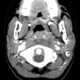

Retropharyngeal hemorrhage